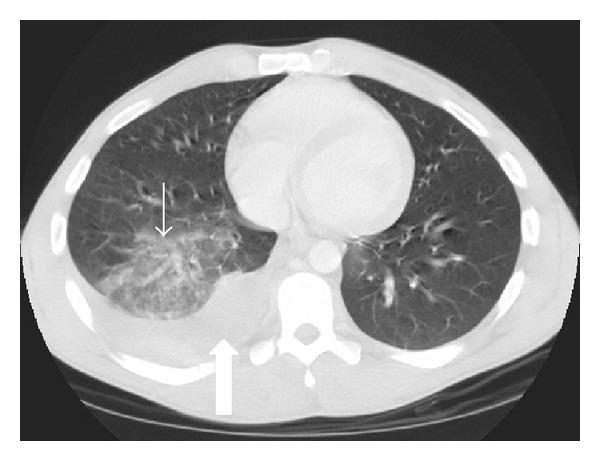

Imaging plays an essential part of chest trauma care. By definition, the employed imaging technique in the emergency setting should reach the correct diagnosis as fast as possible. In severe chest blunt trauma, multidetector computer tomography (MDCT) has become part of the initial workup, mainly due to its high sensitivity and diagnostic accuracy of the technique for the detection and characterization of thoracic injuries and also due to its wide availability in tertiary care centers. The aim of this paper is to review and illustrate a spectrum of characteristic MDCT findings of blunt traumatic injuries of the chest including the lungs, mediastinum, pleural space, and chest wall.

影像学在胸部创伤治疗中起着至关重要的作用。根据定义,在急诊环境中所采用的影像学技术应尽快得出正确诊断。在严重胸部钝性创伤中,多排螺旋计算机断层扫描(MDCT)已成为初始检查的一部分,这主要归因于该技术在检测和鉴别胸部损伤方面具有高敏感性和诊断准确性,还归因于其在三级医疗中心广泛可用。本文旨在回顾并阐述胸部钝性创伤包括肺、纵隔、胸膜腔和胸壁的一系列MDCT特征性表现。